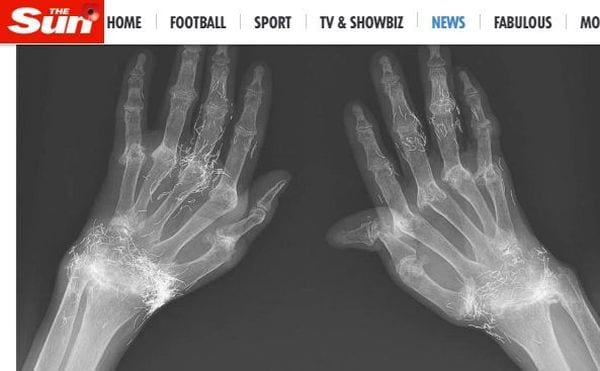

Ovviamente il personale ospedaliero ha proceduto con una lastra, la quale ha mostrato una verità davvero assurda: c’era dell’oro nella pelle della paziente. A raccontare la vicenda è stato il Sun, che ha subito tenuto a specificare che non occorre invocare al miracolo. Loro è motivato, infatti, dall’agopuntura cui si è sottoposta la donna per diversi anni. I filamenti ritrovati nelle dita e sui polsi non sono altro che il residuo degli aghi che per anni le sono stati infilati sotto la pelle per cercare di lenire i suoi dolori. La storia clinica della paziente, infatti, non è esattamente semplice: i primi problemi articolari sono cominciati all’età di 18 anni mentre a 48 le è stata diagnosticata l’artrite reumatoide. È per questo motivo che ha provato la terapia dell’agopuntura.

Le mani della donna, come appare anche dalle foto diffuse, sono ormai deformi. I medici sostengono però che la causa del dolore sia l’artrite, purtroppo degenerativa e incurabile, e non i residui di oro trovati. Un pensiero però non ha abbandonato né la paziente né i medici che l’hanno visitata: probabilmente se avesse seguito una terapia farmacologica i dolori sopportati per anni non sarebbero stati così intensi.